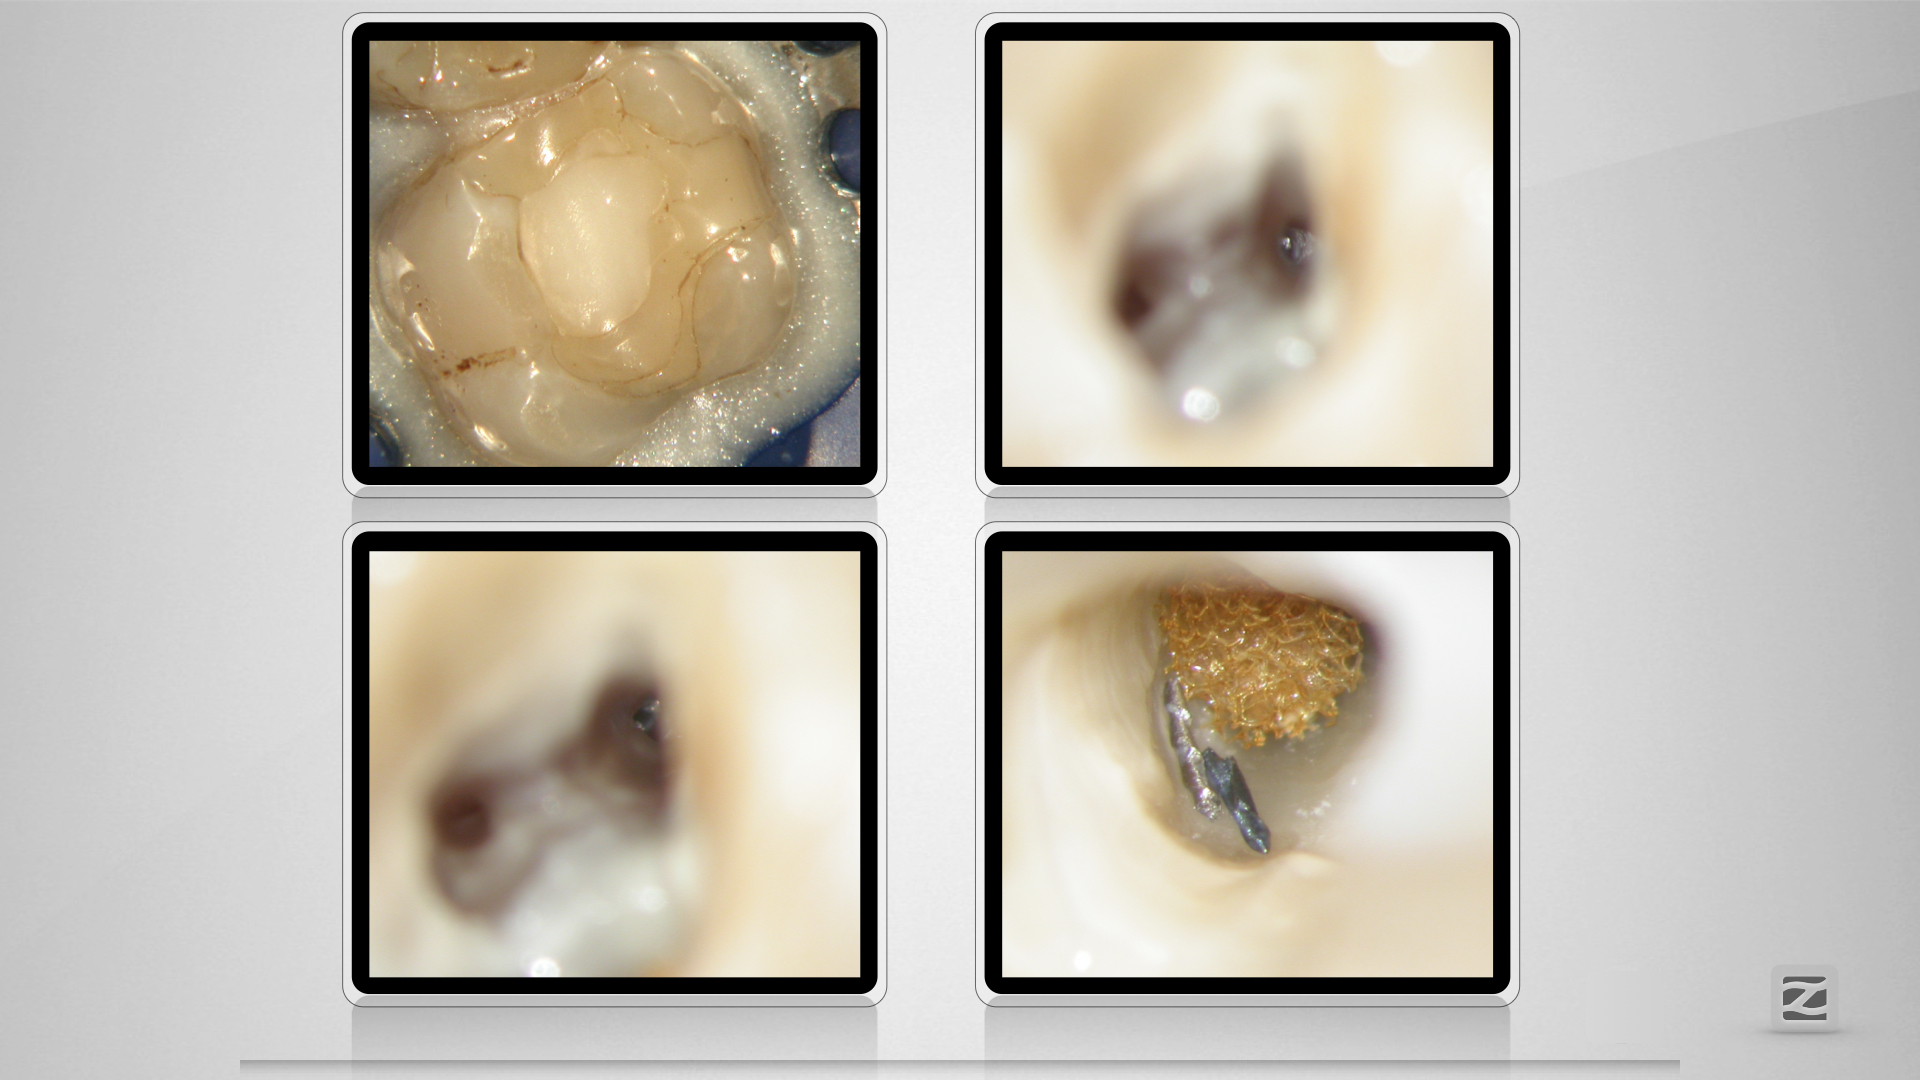

16D.005

Blue(s)